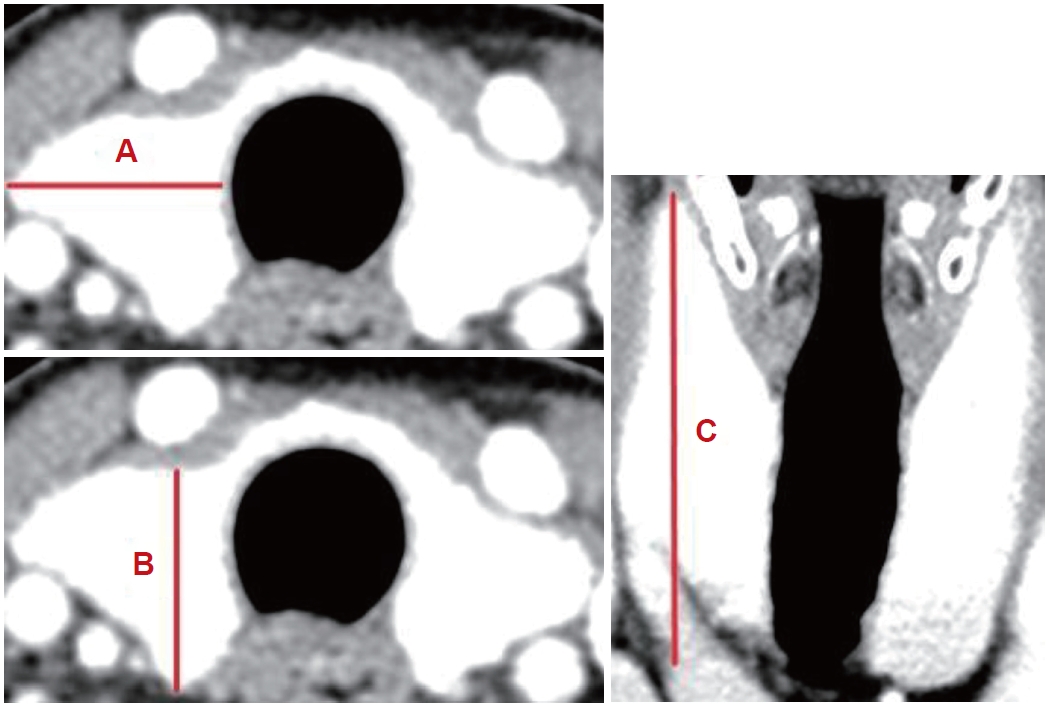

전산화단층촬영검사(CT)를 통한 갑상선 부피 측정본 연구에서는 갑상선의 부피가 커질 경우에도 수술 범위가 커질 수 있으며 이는 수술 후 출혈 및 합병증 발생과 연관이 있을 것으로 가정하여 환자들의 수술 전 갑상선 크기를 측정하였다. 경부 조영증강 전산화단층촬영(enhanced neck CT)은 수술 전 모든 환자에서 시행되는데, Shabana 등[13]은 ‘부피(volume, mL)=최대너비(width, mm)×최대 깊이(depth, mm)×최대길이(length, mm)×교정계수(0.529)’라는 CT를 사용한 갑상선 부피 측정법을 제시하였고, 본 연구에서는 이를 이용하여 갑상선 부피를 측정하였다(Fig. 1). 물론 갑상선의 모양에 따라 이와 같은 방법이 정확하지 않을 수 있으나, 각 수치의 실측값을 바탕으로 부피를 구하였기 때문에 대체로 실제 부피와 비례할 것이라 가정하였다. 편측 갑상선 절제술의 경우 수술 방향에 해당하는 일측 갑상선의 부피만 측정하였으며, 갑상선 전절제술의 경우 양측 갑상선 모두의 부피를 측정하였다.

NotesAuthor Contribution Conceptualization: Phil-Sang Chung. Formal analysis: Sang Min Lee, Min Seok Kim. Methodology: Phil-Sang Chung, Sang Joon Lee, Seung Hoon Woo. Supervision: Phil-sang Chung, Sang Joon Lee, Seung Hoon Woo. Writing—original draft: Sang Min Lee. Writing—review & editing: Sang Min Lee, Phil-Sang Chung, Sang Joon Lee. Fig. 1.Thyroid volume measurement by CT scan. The longest of each section was measured. A: Width. B: Depth. C: Length. Table 1.Demographic and clinical characteristics of patients grouped by drain placement (n=587)